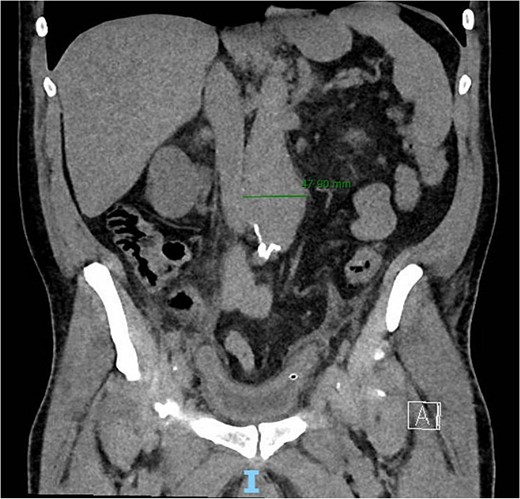

A 56-year-old male with no reported past medical history and a 70 pack year smoking history presented with a chief complaint of lower abdominal pain and body aches. On presentation, the patients white blood cell count (WBC) was 39.6 and procalcitonin was 43.4. Blood cultures were drawn and demonstrated P. mirabilis bacteremia. Computed tomography (CT) abdomen/pelvis was performed as well as ultrasound (US) of scrotum demonstrating a complex fluid collection within scrotal sac that was determined to be a scrotal wall abscess. The patient was started on a course of Unasyn and Urology promptly took him to the operating room (OR) for incision and drainage. Vascular surgery was consulted due to an incidental finding of an abdominal aortic aneurysm on CT measuring 4.7 × 4.6 cm (Figs 1 and 2). The patient was evaluated by the vascular surgery team following his urological procedure and denied any history of abdominal pain or back pain. Physical exam was largely unremarkable however the patient’s bilateral toes were noted to have blue discoloration with motor and sensation intact. Outpatient follow up with routine US scans for the AAA was recommended. Ankle brachial index (ABI) as well as an echocardiography was ordered to further work up the patient’s dusky toes. On Day 2 of hospitalization, ABIs returned showing severe peripheral vascular disease (PVD) and the echocardiography ruled out endocarditis. At this time an angiogram was planned to further the patient’s PVD workup however this was deferred as the patient remained septic with a WBC of 30. Over the course of the next few days the patient refused antibiotics and remained septic with a WBC in the 20s. At this time his toes quickly deteriorated from dusky to dry gangrene. On Day 8 of hospitalization the patient remained septic and was now complaining of new onset mid-abdominal pain. Emergent CT showed AAA was now 7.7 × 7.8 cm with periaortic fat stranding concerning for impending rupture (Figs 3 and 4). The patient was taken emergently to the OR for open repair. Upon visualization, the abdominal aortic aneurysm was clearly infected with signs of impending rupture on the left lateral wall and purulent material including infected thrombus. Tissue was cultured however showed no growth, likely due to the fact that the patient had been on antibiotic therapy for a week at this time. Reconstruction with an aorto-biiliac bypass using rifampin-soaked dacron graft was performed. A piece of omentum was mobilized over the graft and the retroperitoneum was closed over it. The abdomen was left open for a return to the OR for a second look which showed no concerns for bowel ischemia, worsening infection or bleeding. On post-op Day 5 the patient was extubated, off pressor support, and transferred to the floor. The patient’s postoperative course was unremarkable except for bilateral toes demarcating to dry gangrene.

Frontal CT angiography of the abdomen and pelvis demonstrating 7.75 cm AAA with fat stranding.